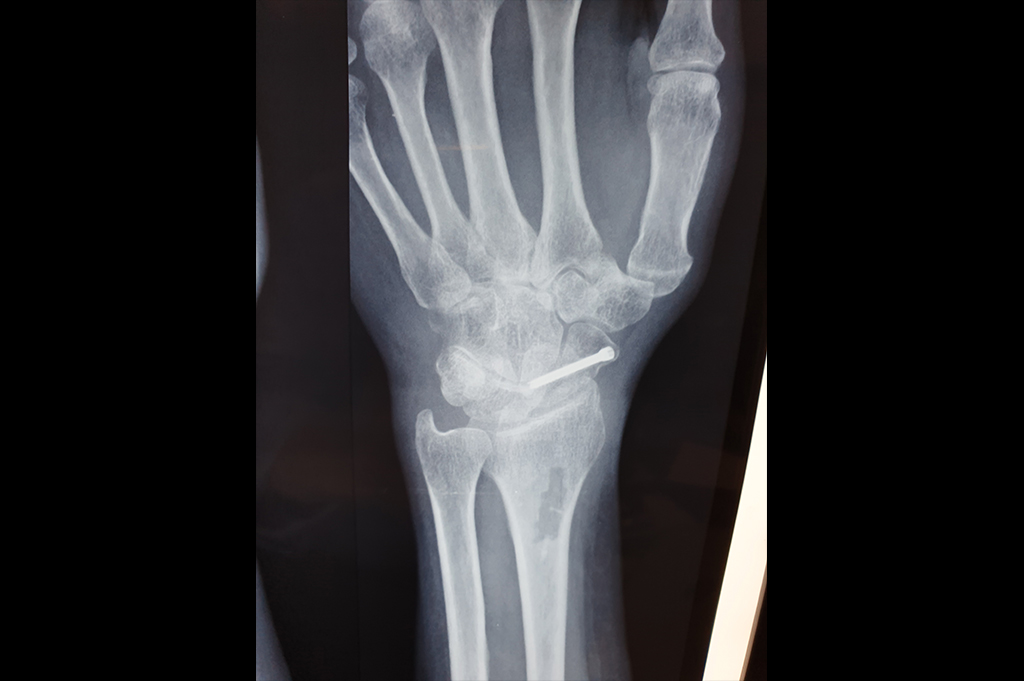

Scaphoid